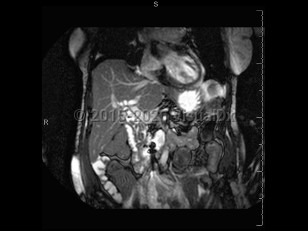

Pyogenic liver abscessPyogenic liver abscess